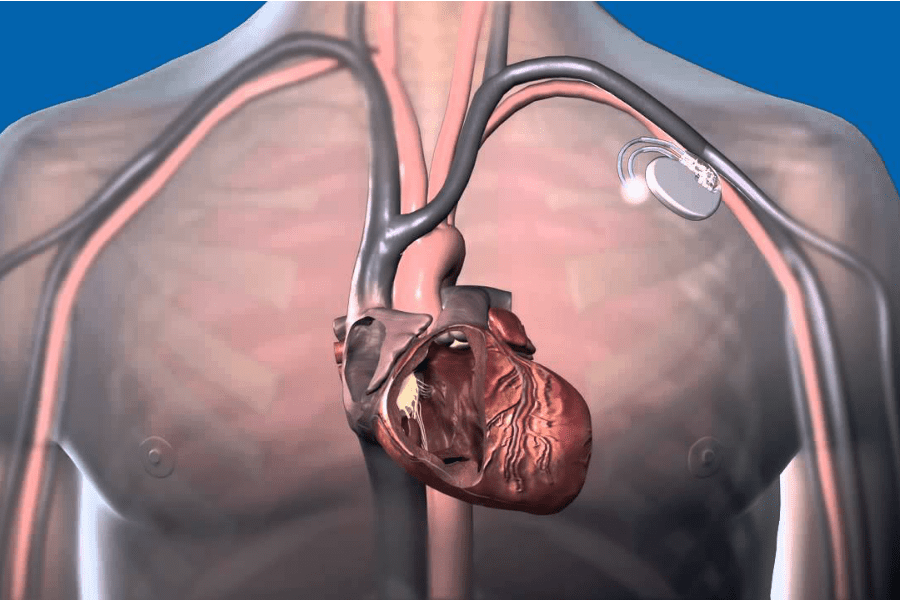

Pacemaker e defibrillatori difettosi: due morti negli Usa, allarme anche in Italia. Le cardiochirurgie italiane e estere sono state informate del pericolo che i pazienti stanno correndo.

Centinaia di pacemaker e defibrillatori prodotti dalla multinazionale americana St. Jude Medical risulterebbero difettosi e dunque costituirebbero un serio pericolo per la vita del paziente. I problemi che sono stati segnalati sono causati dal prematuro esaurimento delle batterie e dal corto circuito dei dispositivi. Proprio a causa di queste problematiche due persone negli Stati Uniti sono decedute.

I reparti di cardiochirurgia italiani e il Ministero della Salute hanno segnalato il pericolo alle varie Asl. I micro defibrillatori fabbricati prima del 2015 sono 398.740 e potrebbero portare, ora, gravi rischi per la salute dei pazienti cardiopatici dovuti all’esaurimento delle batterie. L’azienda nel diffondere la notizia ha precisato che “la sostituzione profilattica del dispositivo non è raccomandata, perché le complicazioni derivanti da una sostituzione sono maggiori rispetto al danno associato al corto circuito”.

Per quanto concerne i defibrillatori sono 46 su 841 quelli contenenti depositi di litio. Oltre ai due decessi sono stati registrati anche 37 casi di pericoloso senso di vertigini e dieci di sincope. Dunque è tassativamente necessario un controllo dell’apparecchio e il probabile mal funzionamento dei defibrillatori può essere riconosciuto dal medico mediante una visita o un monitoraggio remoto. In merito a tale problema, il Ministero della Salute ha trasmesso delle raccomandazioni per la gestione dei pazienti. Il medico ha l’onere di avvisare i pazienti portatori di tale apparecchio, istruirli a riconoscere i segnali di malfunzionamento, tra cui quello delle batterie in esaurimento che di solito concerne in un allarme vibrazionale. Tramite il modulo di ricerca messo a disposizione dalla St. Jude Medical, i pazienti possono verificare ed accertarsi se il dispositivo in loro possesso fa parte proprio della categoria a rischio.